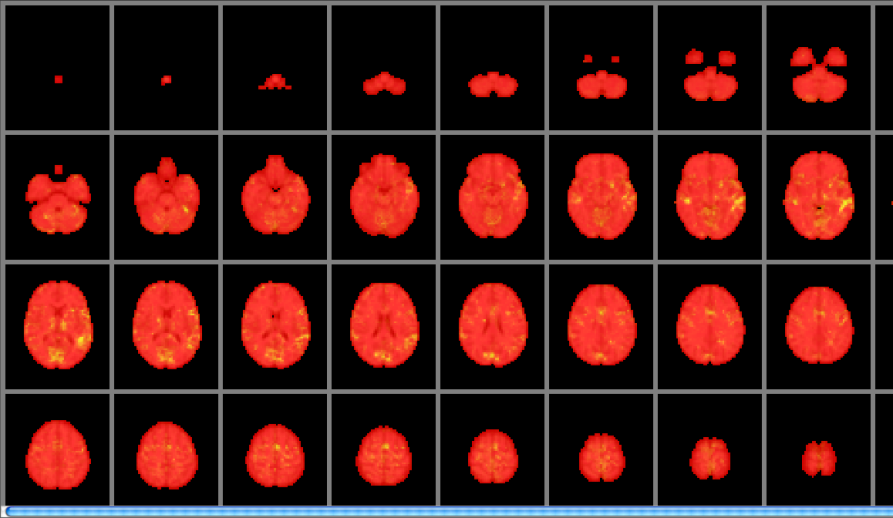

Refer to caption

Figure 1: Ground truth image for the active region in the simulation of a Gaussian process prediction of z-scores given a hypothetical behavioural measure (normalised between 01010-1).

To create a dependence of the fMRI signal on the behavioural score, two regions of activity are defined where were turned on or off depending on the behavioural score. These regions of ground truth activity are shown in figure 1 and referred to as region 𝒜𝒜{\mathcal{A}} and {\mathcal{B}}. The degree of added activity in each region was weighted depending on on the normalised behavioural scores. More precisely, if voxel v𝑣v is in region 𝒜𝒜{\mathcal{A}}, written as δ(v𝒜)𝛿𝑣𝒜\delta\left(v\in{\mathcal{A}}\right) where δ()𝛿\delta\left(\cdot\right) is the indicator function, and the subject has the behaviour score α𝛼\alpha then

is the effective magnitude of the signal at v𝑣v that is added to the base-line fMRI time series. Thus, the degree of activity is gradually shifted with one ground truth region (Region 𝒜𝒜{\mathcal{A}}) active at higher normalised behavioural scores and the other region at lower scores.